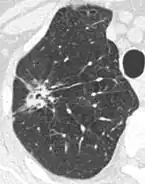

- Vascular convergence is where vessels converge to a nodule without adjoining or contacting the edge of the nodule, and is mainly seen in peripheral subsolid lung cancers.[9] It reflects angiogenesis.[9]

Air bronchograms is defined as a pattern of air-filled bronchi on a background of airless lung, and may be seen in both benign and malignant nodules, but certain patterns thereof may help in risk stratification.[9]